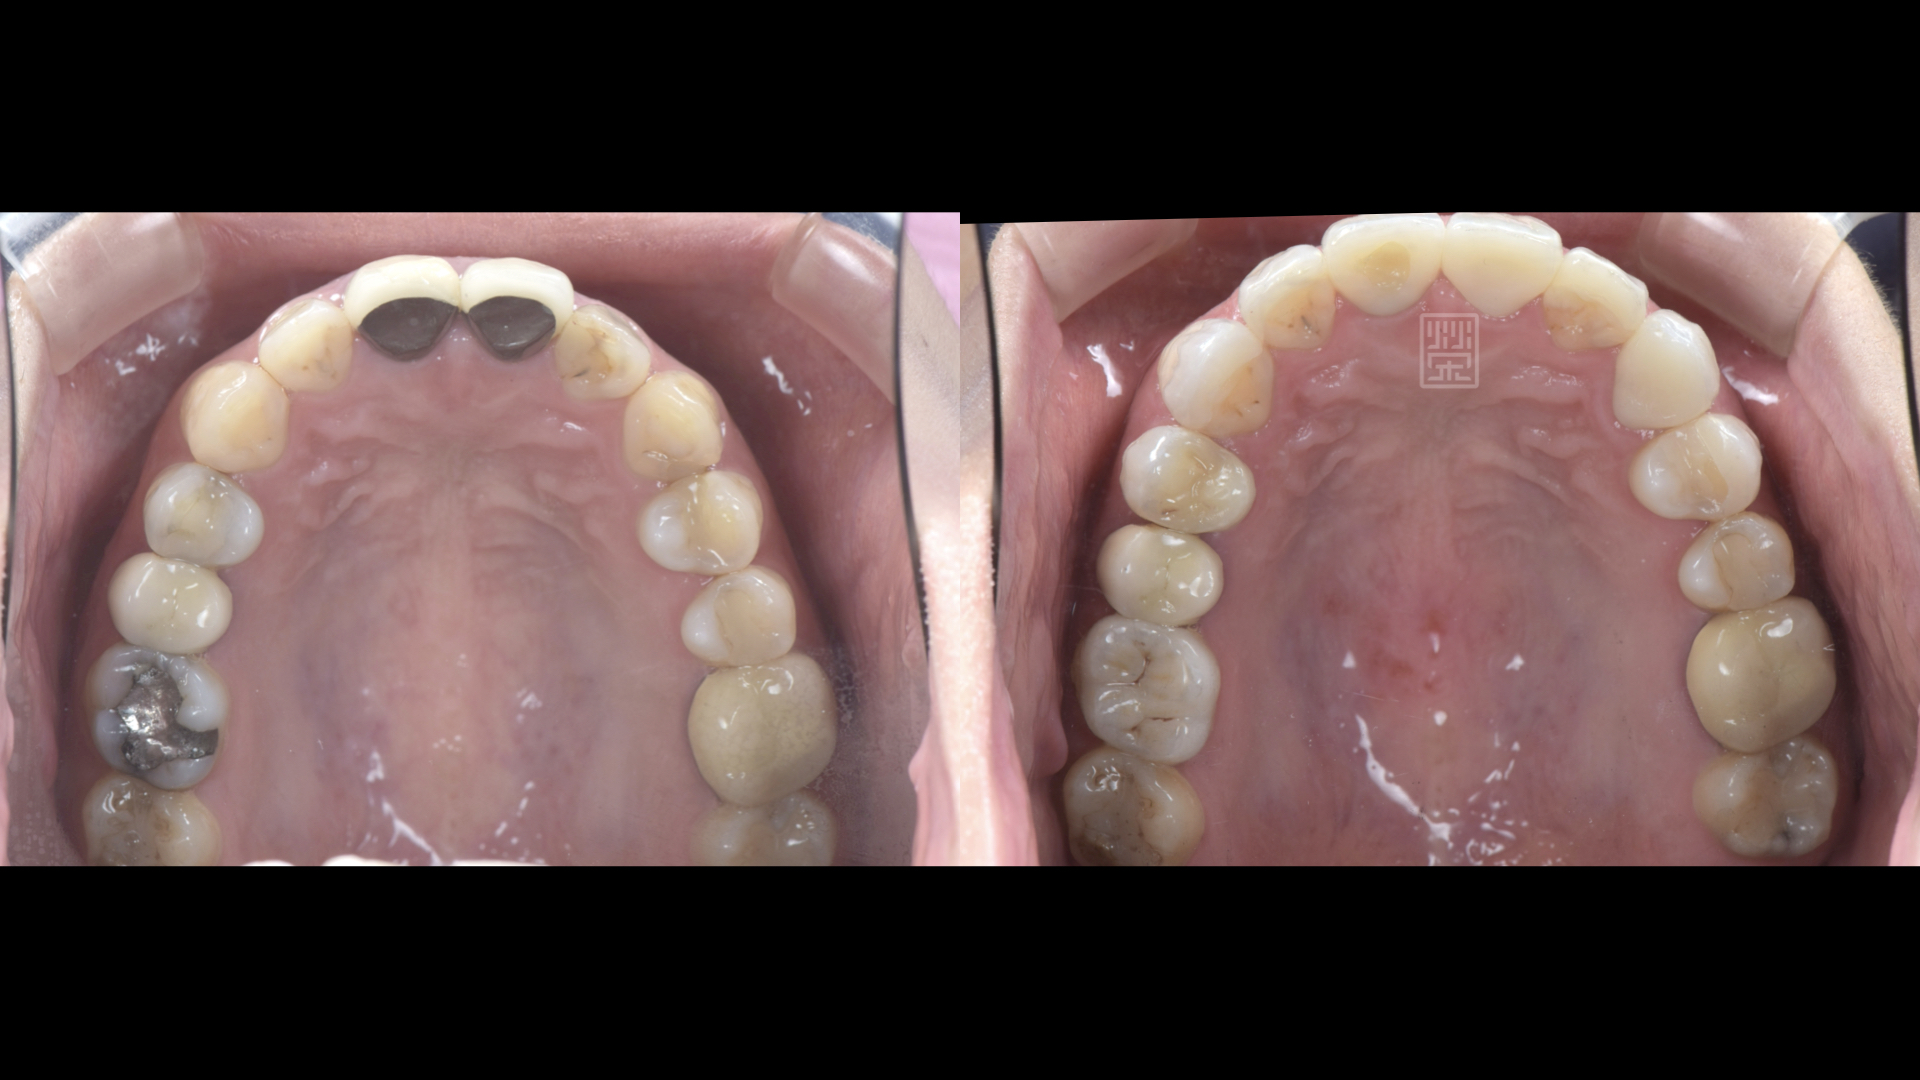

前後對比